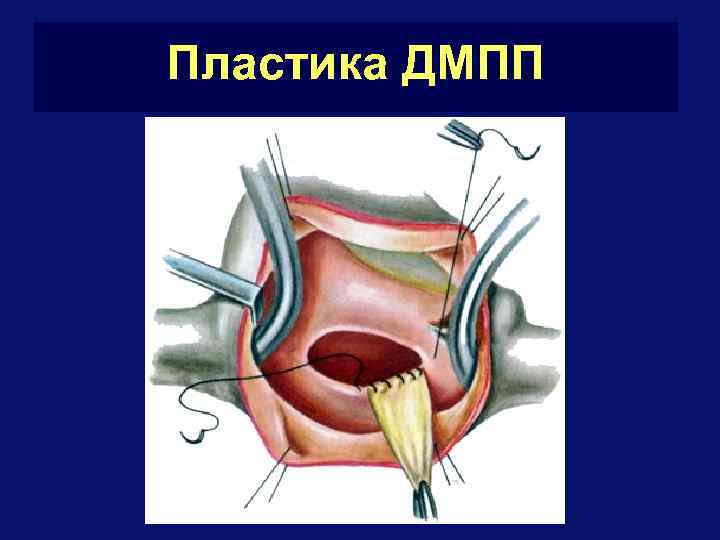

Лечение ДМПП q q Показания к операции – наличие ХСН, увеличение АД в Ла При нормальном АД в Ла и отсутствии жалоб при небольших дефектах – наблюдение (у 3% закрываются самостоятельно) Операция – через правое предсердие – ушивание (до 3 см) или пластика заплатой (более 3 см) Летальность – 2%

Пластика ДМПП